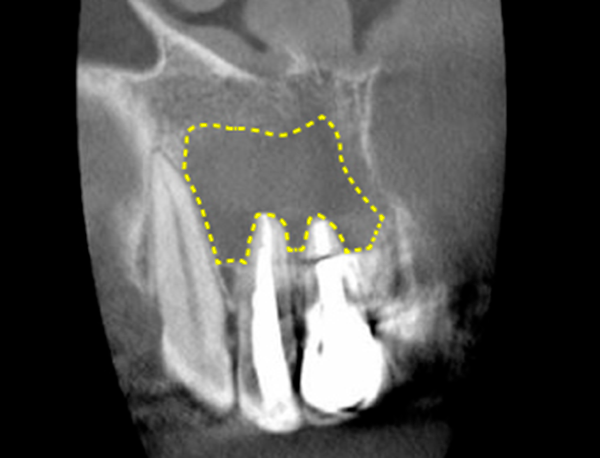

The area I thought I had cleaned up to the apex of the root was actually the intersection area far above the apex. (Figure 3)

In other words, the nerve had been left out.